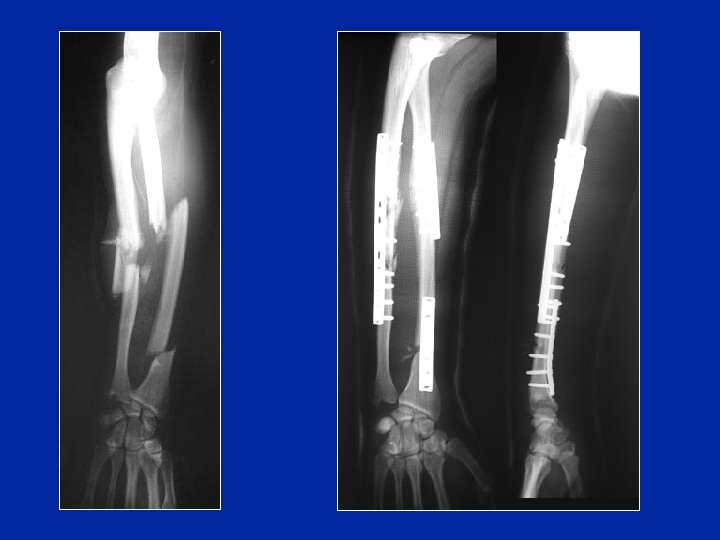

Fracture de Galeazzi Fracture du radius + luxation distale du cubitus

Traitement de la fracture de Galeazzi Après reconstruction et ostéosynthèse du radius, le cubitus se réduit

TRT chirurgical s’adresse à l’adulte et à quelque fr chez le grand enfant. -les plaques vissées indiquées chez l’adulte ; permettent une rééducation précoce. -l’embrochage : utilisé surtout chez l’enfant. -le fixateur externe : utilisé dans les Fr complexes et les délabrements musculaires.

Traitement chirurgical Fractures irréductibles de l’enfant Fractures déplacées de l’adulte Mobilisation rapide Consolidation en 3 mois

Déplacement sous plâtre ostéosynthèse par plaques